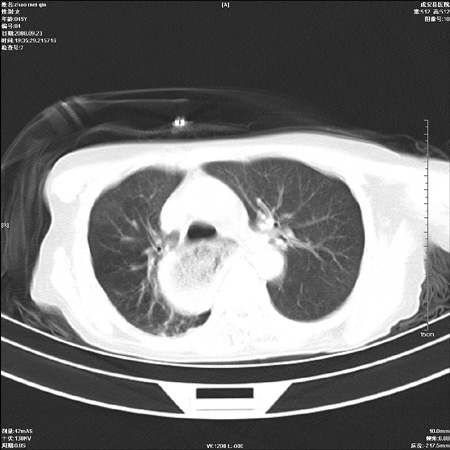

标题: CT15861:女 60 外伤后1小时 胸疼 [打印本页]

标题: CT15861:女 60 外伤后1小时 胸疼

外伤后1小时 胸疼 是外伤后引起的吗?

食道扩张明显下端逐渐变窄,倒像贲门失迟缓

食道ca术后胸腔胃,右肺挫伤?

非外伤性改变,典型的贲门失迟缓症

食道扩张明显下端逐渐变窄,大量食物存留,象贲门失迟缓症。